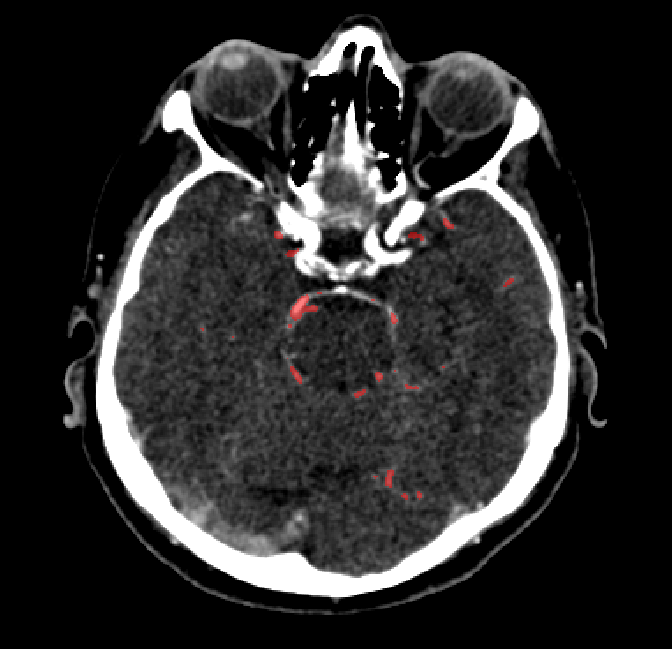

Refer to caption

(a) Axial (top-down) view.

(b) Coronal (back-front) view.

(c) Sagittal (left-right) view.

Figure 3.3: Generated vessel structures with spatial target growth incentive. The target volume was a vessel density atlas created by averaging the ground truth of patients in our data set.

Another use of the vessel atlas is to determine if a node is out of bounds. This is done by checking if the atlas has a value of 0 at the node’s position. If a leaf node is too far out of the brain, the branch is discontinued (the leaf will never be selected to spawn a child). On top of this, in order to make the overall structure more realistic, a different atlas was used for each of the two hemisphere root nodes. Such atlas would only have non-zero values for one brain hemisphere. This causes the resulting vessel structures to no longer cross over between hemispheres. A resulting example structure can be seen in Figure 3.3.